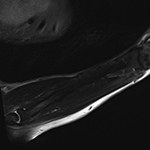

Shading Artifact. (A) Incomplete coil coverage results in dark signal obscuring the soft tissues adjacent to the olecranon at the periphery of sagittal STIR image of the forearm in a patient with cellulitis and concern for abscess. (B) Axial T1-weighted post-contrast fat-saturated image obtained following coil repositioning demonstrates abscess (arrow) in the previously obscured region.